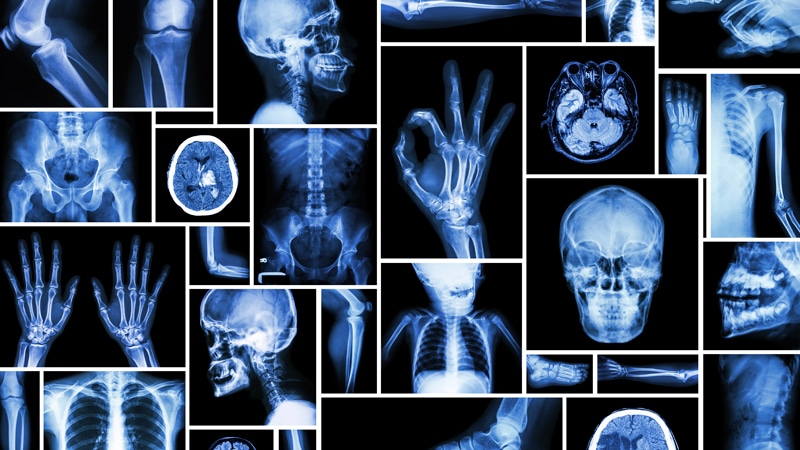

رادیولوژی یا علم تصویربرداری، شاخه‌ای از پزشکی است که با انرژی تابشی در تشخیص و درمان بیماری‌ها سر و کار دارد. رادیولوژی که همچنین به عنوان تصویربرداری تشخیصی نیز شناخته می‌شود، ابزاریست که پزشکان می‌توانند توسط آن، آنچه را که در بدن اتفاق می‌افتد دیده و درک کنند.

در رادیولوژی از اشعه استفاده شده و از تصاویر استفاده نمی‌شود. این نوع تصویربرداری مستقیما از اشعه یونی استفاده می‌کند. به طور کلی می‌توان گفت رادیولوژی یک تخصص در پزشکی است که به تولید تصاویر داخلی بدن از طریق عوامل مختلف فیزیکی، میدان مغناطیسی و غیره می‌پردازد و از این تصاویر برای تشخیص و در حد کمتری برای پیش آگاهی و درمان بیماری‌ها استفاده می‌کند.

هدف از رادیولوژی تشخیص مشکلات داخلی، جلوگیری از ایجاد صدمه و درد است؛ زیرا پزشکان را قادر می‌سازد تا بیماری‌ها را سریع‌تر و دقیق‌تر تشخیص دهند. این شاخه از پزشکی تخصصی از تجهیزات و طیف وسیعی از تکنیک‌ها برای گرفتن تصاویر از داخل بدن، استفاده می‌کنند.